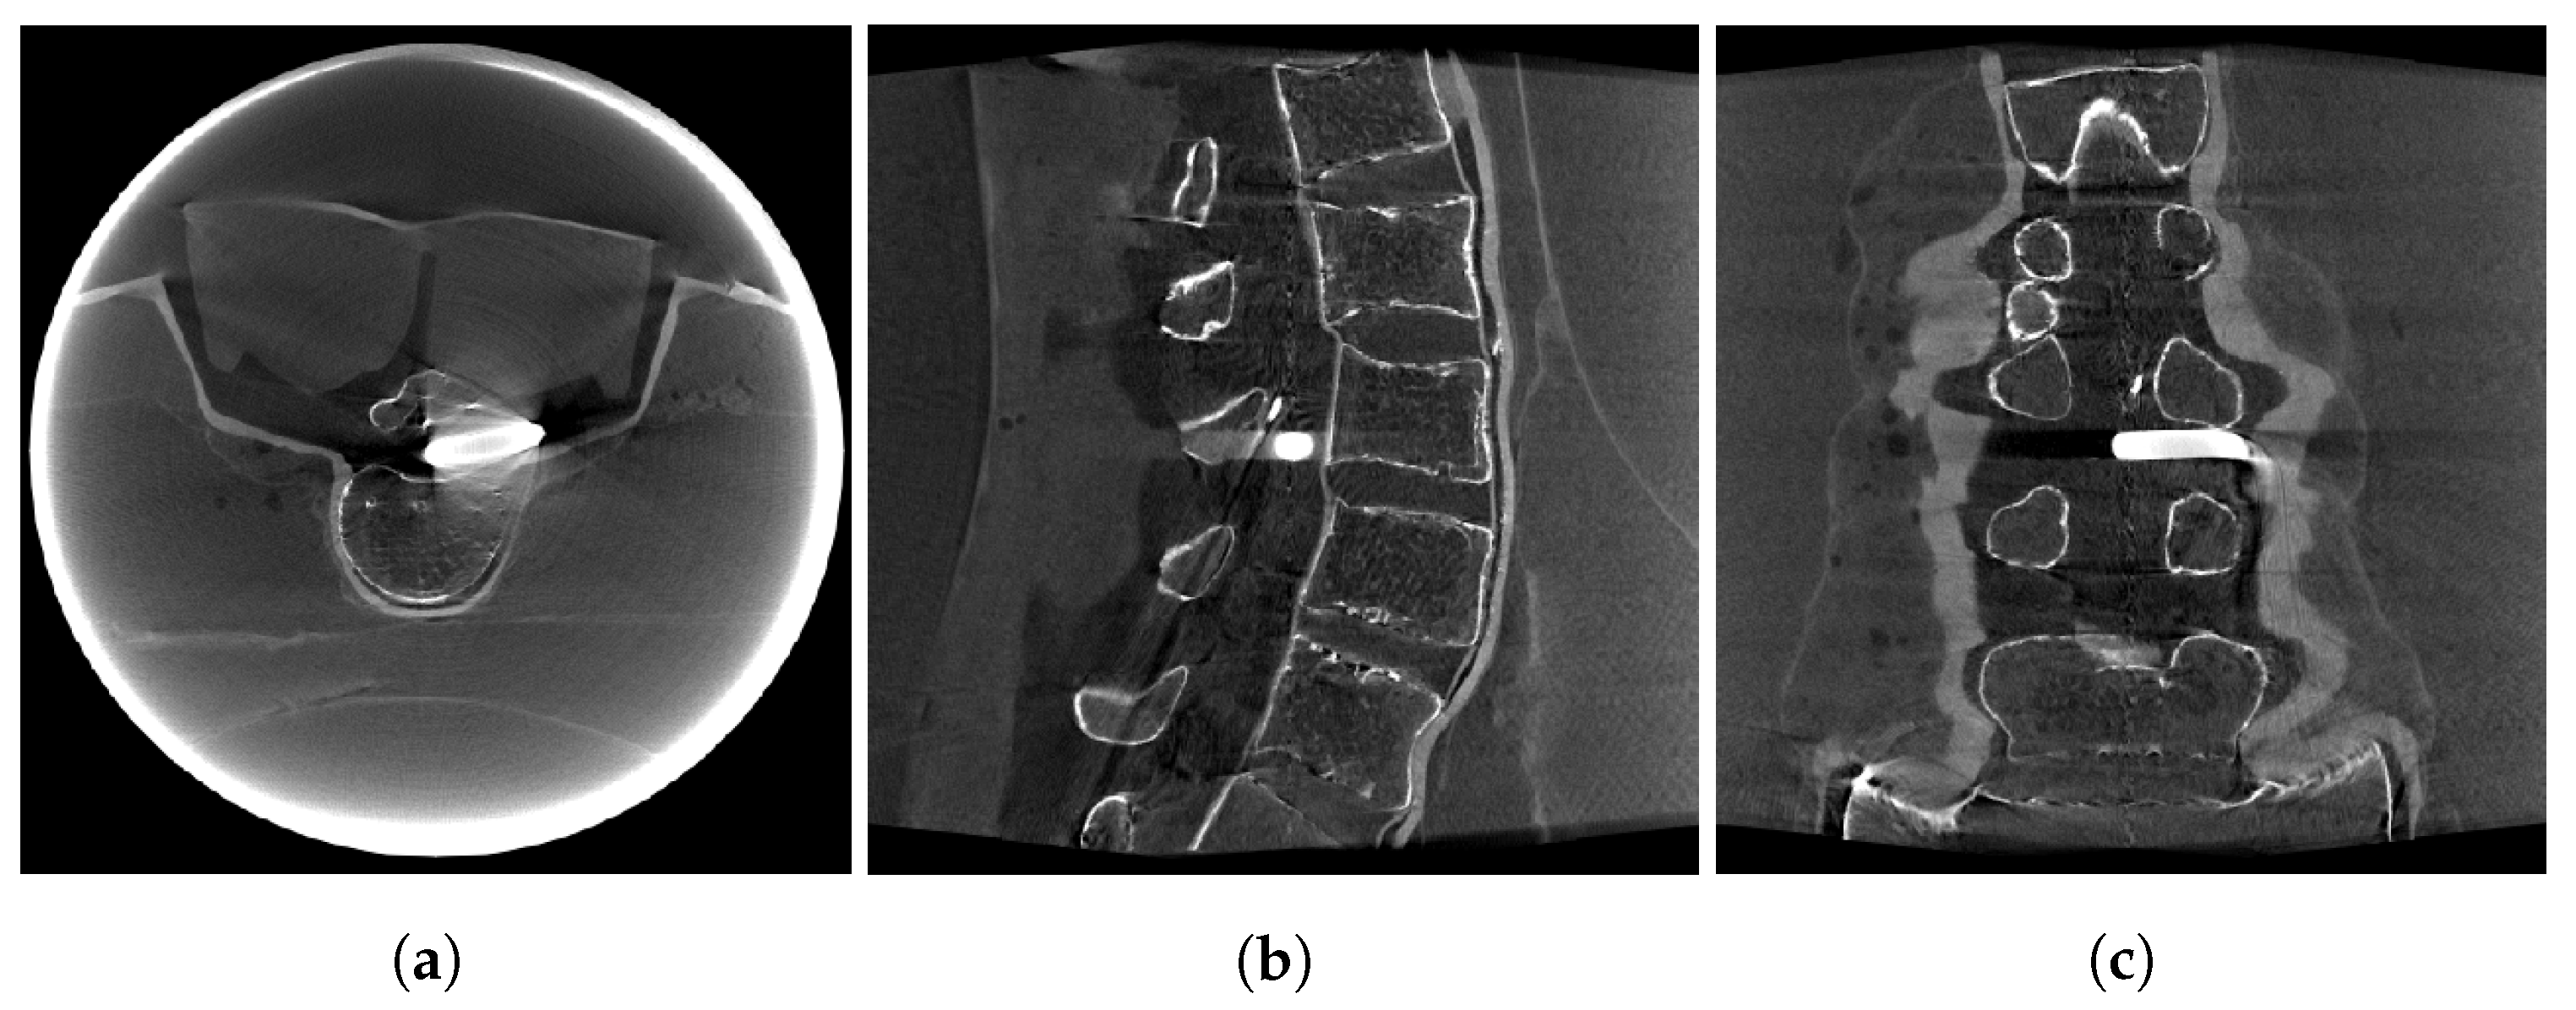

2.4. Image Data